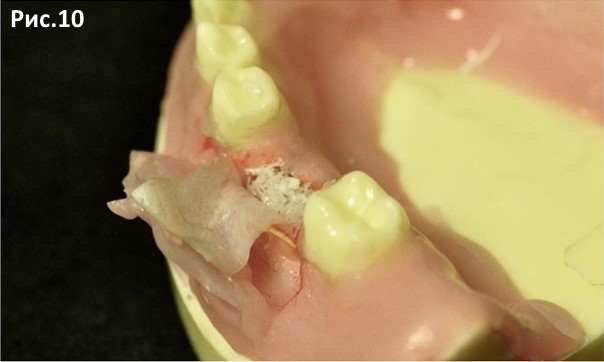

Помещаем материал в поднадкостничный карман. Рис.10